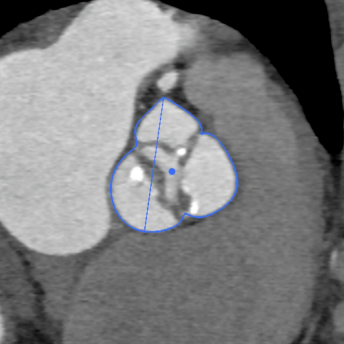

为确保手术过程万无一失,手术后患者能尽快恢复,团队全体成员反复沟通、讨论,应用医用软件分析出多方位参数,并制定各种风险的应急处理方案。

全麻后,成功穿刺右股动脉,通过穿刺点输送系统将瓣膜输送至病变的主动脉瓣处,经过严密地心电监护、心脏食道超声引导,手术团队在心室快速起搏下,使得收缩压降到 60 mmHg、脉压差小于 10 mmHg,此时释放人工生物瓣膜取代自身病变的瓣膜,食道超声检查无瓣周漏,人工瓣膜工作正常,手术完美结束。